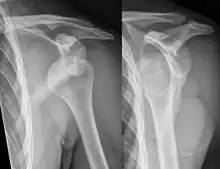

X-ray at left shows anterior dislocation in a young man. X-ray at right shows the same shoulder after reduction and internal rotation, revealing a Bankart lesion and a Hill-Sachs lesion.

In over 95% of shoulder dislocations, the humerus is displaced anteriorly.[7] In most of those, the head of the humerus comes to rest under the coracoid process, referred to as sub-coracoid dislocation. Sub-glenoid, subclavicular, and, very rarely, intrathoracic or retroperitoneal dislocations may also occur.[8]

A Hill–Sachs lesion is an impaction of the head of the humerus left by the glenoid rim during dislocation.[6] Hill-Sachs deformities occur in 35–40% of anterior dislocations. They can be seen on a front-facing X-ray when the arm is in internal rotation.[9] Bankart lesions are disruptions of the glenoid labrum with or without an avulsion of bone fragment.